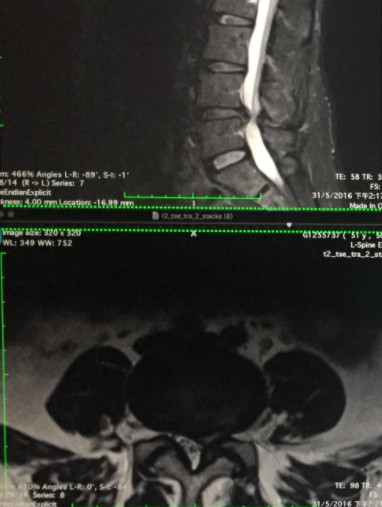

椎間盤切除後再次突出,怎麼辦, 這是很多病人當知道自己的椎間盤再次突出後常問的問題。50歲李女士是家庭主婦,2016年5月彎腰拿重物後便出現腰腿痛,作磁力共振掃描後發現腰椎第4、5節椎間盤0.7公分向中左突出(見圖一),壓到少許馬尾神經及左方神經根。

(圖一) 2016年5月腰椎第4,5節椎間盤 0.7cm向中左突出